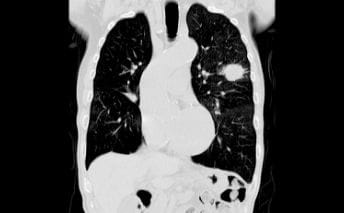

CT(コンピューターX線撮影)

CTはX線を使った人間の身体の透視画像を作ります。カメラが身体の周りをグルグル回り、輪切りの画像を何枚も撮り、単純な断層画像だけでなく、それらをつなぎ合わせて立体的な画像の作成もできます。

- 特長

- X線吸収差の大きい骨や肺の描出に優れている